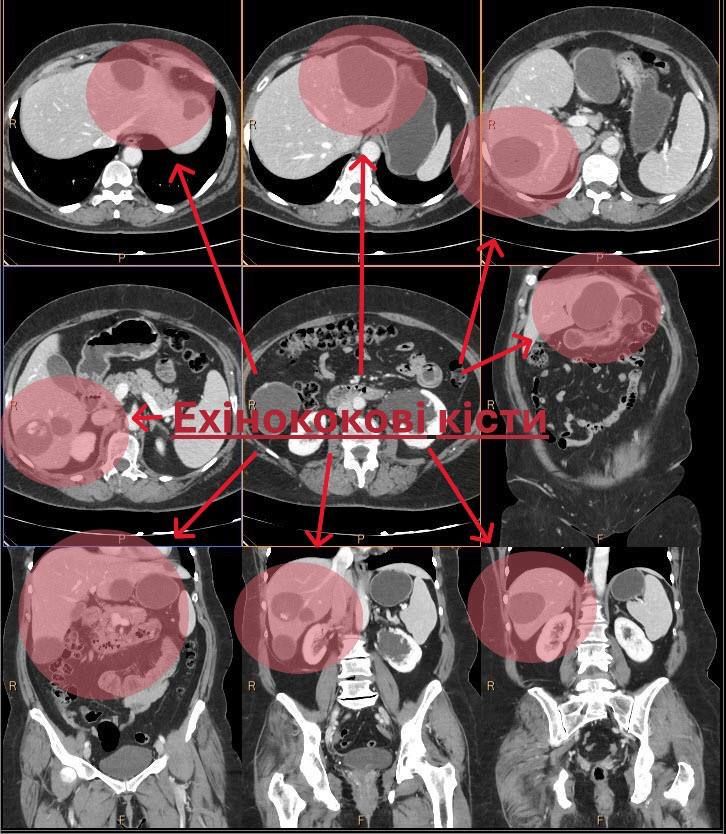

До медиків звернулася жінка зі скаргами на слабкість, підвищену температуру, відчуття важкості та розпирання у правому підребер’ї та епігастрії. Фахівці направили її на аналіз на ехінокок і КТ, де виявили множинні кісти. Єдиним способом допомогти була операція.

Команда лікарів - Назарій Шарафан, Іван Нечипорчук, лікар-інтерн Анастасія Омельянчук та анестезіолог Юрій Коваль - провела втручання лапароскопічно. Всі патологічні осередки видалено, здорова тканина печінки збережена. Пацієнтка після операції почувається добре та вже проходить відновлення.